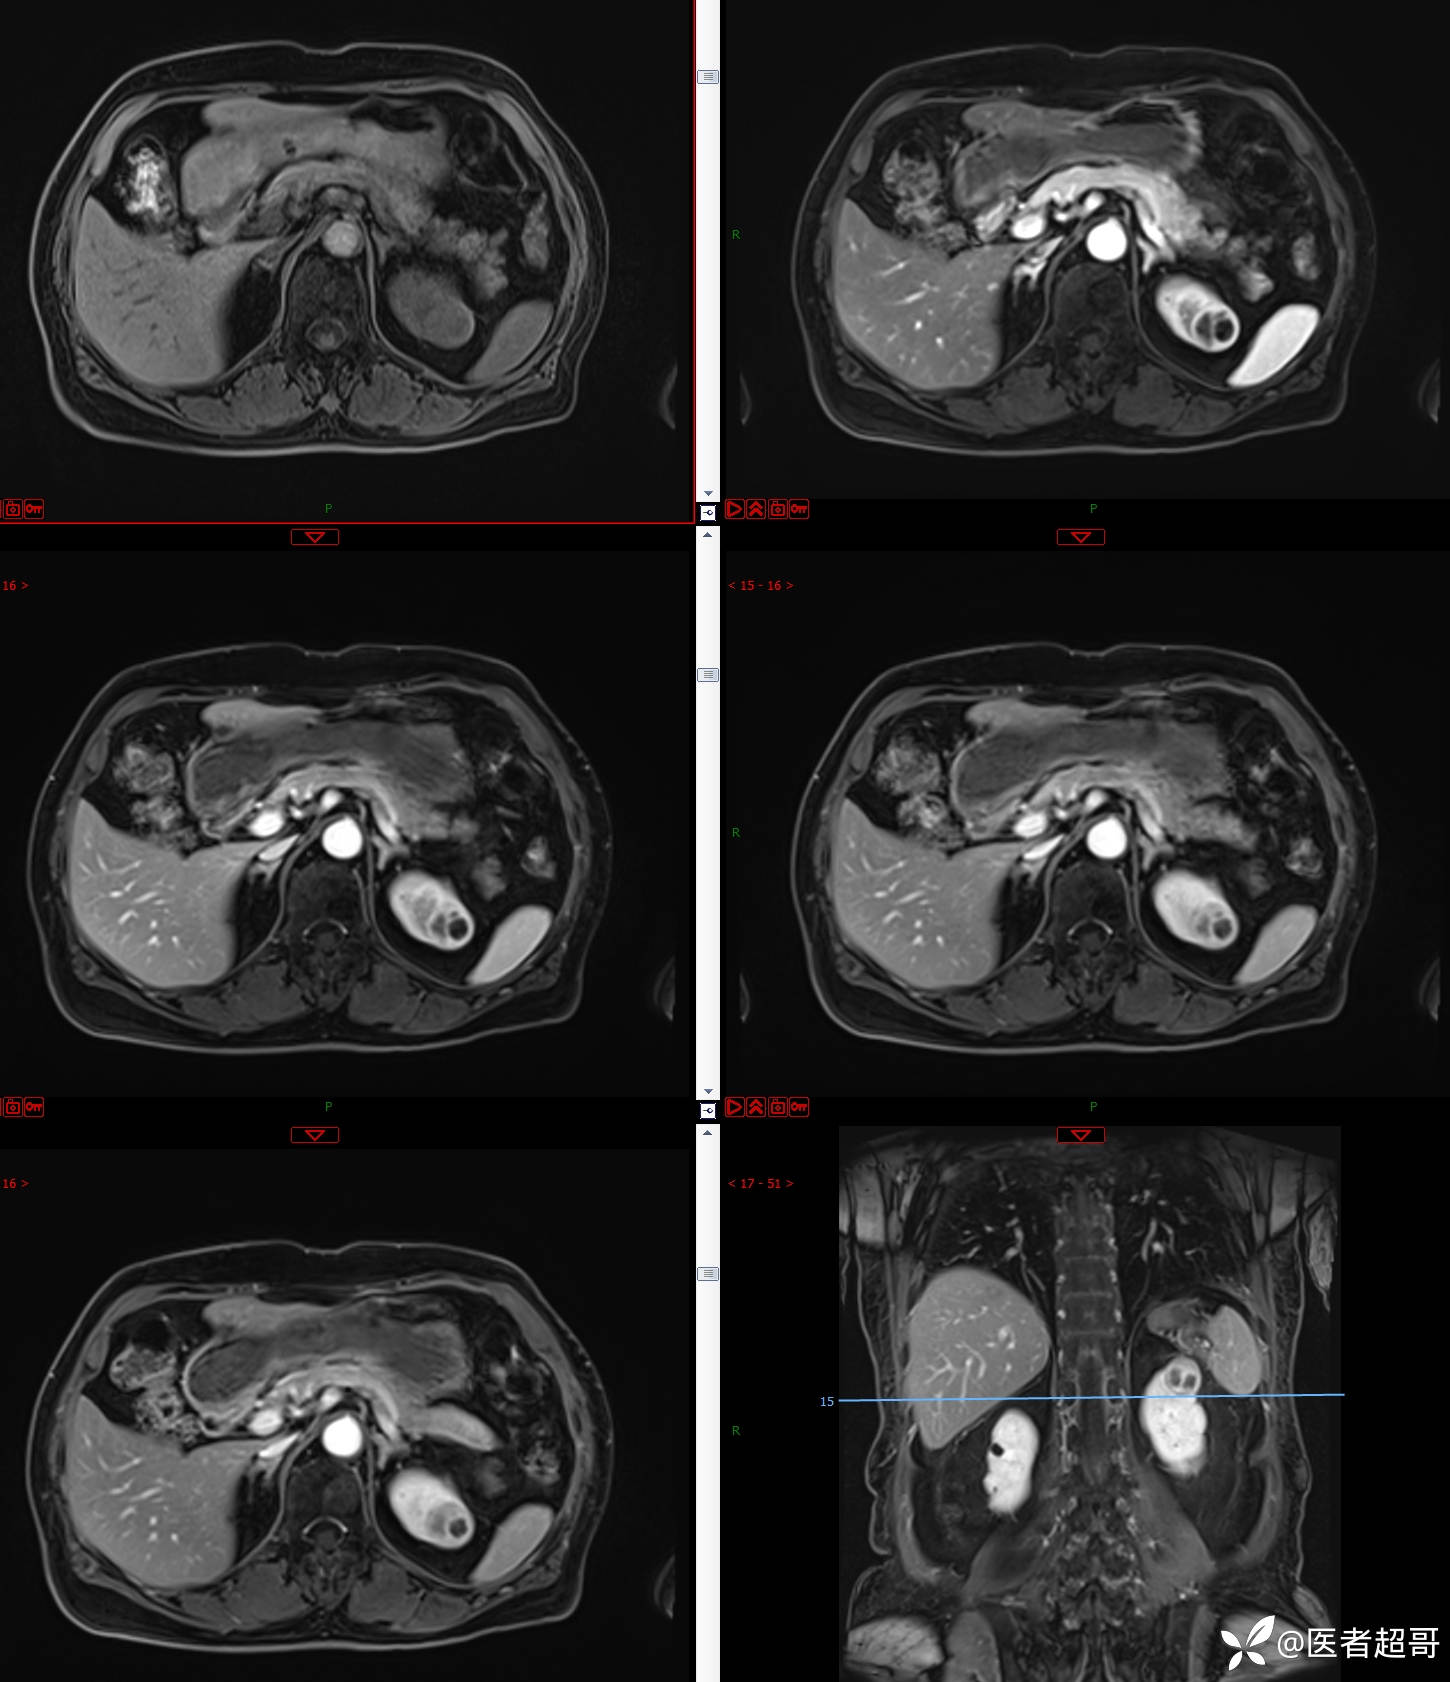

左肾占位2个月就诊,有病理,请分析!

主 诉:查体发现左肾占位2月。

现病史:患者自述2月前于镇中心卫生院行腹部超声发现:左肾实性占位。患者无尿频尿急尿痛,无发热寒战,无恶心呕吐。未行特殊治疗。现患者为求进一步诊治,就诊我院,门诊以“肾肿物”为诊断收入院,患者自发病以来,神志清,精神可,饮食可,睡眠一般,大便正常,体重未见明显改变。